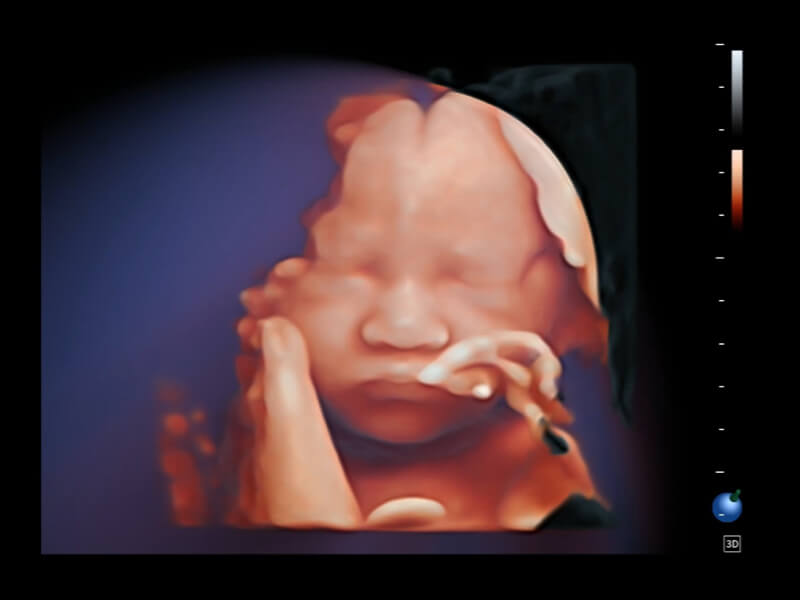

夢(mèng)溪?P80以“關(guān)愛(ài)女性”為基石,提供全方位的解決方案,量身定制以滿(mǎn)足女性的健康需求,涵蓋婦科、生殖健康檢查、產(chǎn)前篩查及產(chǎn)后康復(fù)等領(lǐng)域。